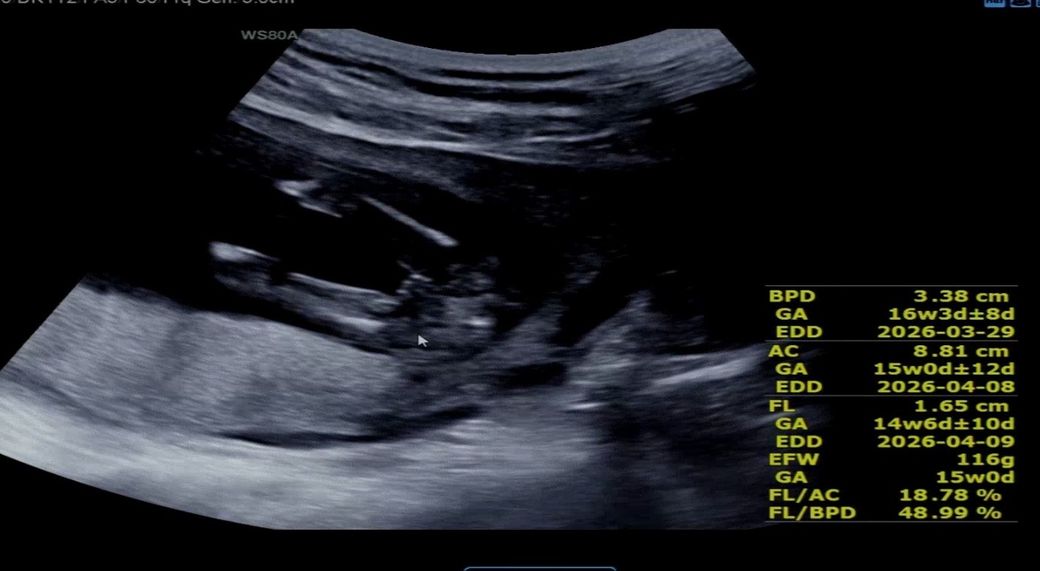

12주 때 8-90% 아들이라고 하셨는데

오늘(15주) 초음파 봤더니 딸이 거의 확실하다고 하시네요

초음파 사진 첨부합니다

왼쪽이 12주, 오른쪽이 15주에요

외부생식기가 늦게 발달하는 경우에 딸 -> 아들로 바뀌는 경우는 종종 있습니다만, 15주가 지나서 결정되는 경우는 드문 편입니다. 초음파 상에서도 외부생식기의 발달은 없는 것으로 보입니다.